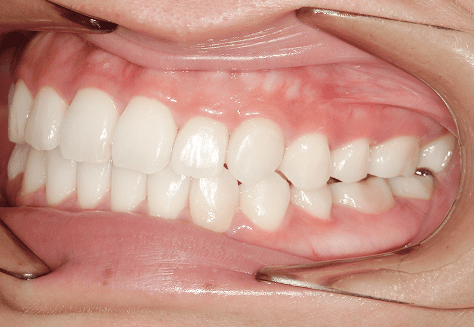

M.M

治療前

治療後

主訴

嚙み合わせが悪い。八重歯が気になる。

診断

叢生・反対咬合

年齢/性別

10代/女性

抜歯部位

非抜歯

使用装置

インビザラインファースト→インビザラインフェーズⅡ(部分的にワイヤーにて処置)

保定装置

上下ビベラリテーナー

料金

初回資料採得・・・・・・・30,000円

診断料・・・・・・・・・・0円

動的治療終了時資料採得・・5,500円 -

基本料金

円ファースト時:450,000円

フェーズⅡ時:240,000円 -

診察料金

ファースト時:0円×16回

フェーズⅡ時:5,500円×9回

ワイヤー併用時:8,800円×2回 -

治療期間

2年7カ月